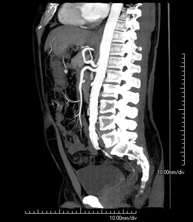

- Aortoiliac CT angiography

A non-invasive diagnostic test that involves examining the iliac arteries and abdominal aorta, obtaining high-definition anatomical images using CT (computed tomography) equipment and iodinated contrast dye. With the aid of workstations specialised for arterial studies, the image quality supports 2D and 3D reconstructions. This test is particularly recommended as a pre-surgical study (vascular map) prior to percutaneous or surgical interventions on the abdominal aorta, as a complementary study in patients with lower limb ischaemia, etc.